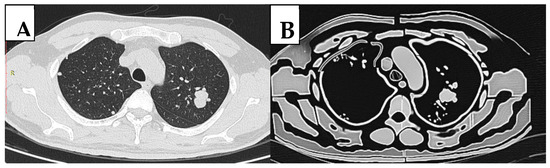

2.1. Selection of Sample Case and Image Segmentation